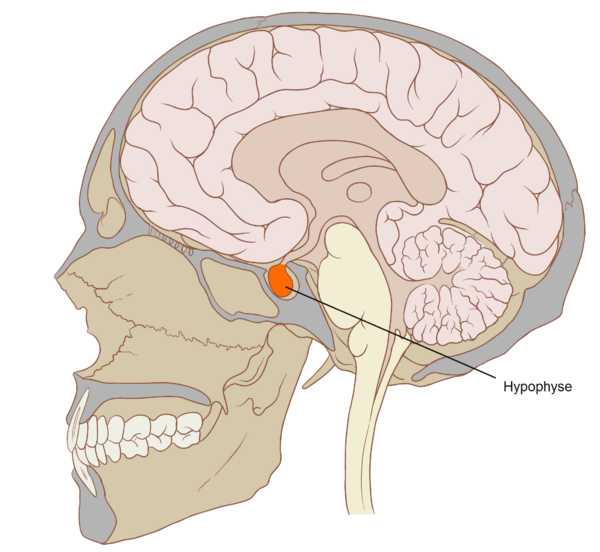

Гипо́физ (лат. hypophysis — отросток; синонимы: ни́жний мозгово́й прида́ток, питуита́рная железа́) — мозговой придаток в форме округлого образования, а также орган внутренней секреции, отвечающий за рост человека, он расположен на нижней поверхности головного мозга в костном кармане, называемом турецким седлом, вырабатывает гормоны, влияющие на рост, обмен веществ и репродуктивную функцию. Является центральным органом эндокринной системы; тесно связан и взаимодействует с гипоталамусом мозга.

Гипофиз располагается в основании головного мозга (нижней поверхности) в гипофизарной ямке турецкого седла клиновидной кости черепа. Турецкое седло прикрыто отростком твёрдой оболочки головного мозга — диафрагмой седла, с отверстием в центре, через которое гипофиз соединён с воронкой гипоталамуса промежуточного мозга; посредством её гипофиз связан с серым бугром, расположенным на нижней стенке III желудочка. По бокам гипофиз окружён пещеристыми венозными синусами.